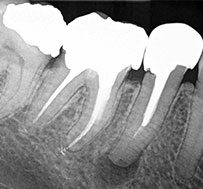

There's no denying the natural abilities of GuttaCore. After heated, it flows and follows the natural anatomy of the root canal system. Simply put, it travels into areas where traditional cold gutta-percha stops. Move your obturation in the right direction. Go with GuttaCore.

GuttaCore obturators are designed to easily create post space. The crosslinked gutta-percha core removes easily* and the handle can be removed by bending to either side of the canal wall.

Sealing efficacy of system B versus Thermafil and Guttacore obturation

techniques evidenced by scintigraphic analysis

Manuel Marques-Ferreira, Margarida Abrantes, Hugo-Diogo Ferreira,

Francisco Caramelo, Maria-Filomena Botelho, Eunice-Virgínia Carrilho

J Clin Exp Dent. 2017 Jan; 9(1): e56–e60. Published online 2017 Jan 1. doi: 10.4317/jced.52889

PMCID: PMC5268114